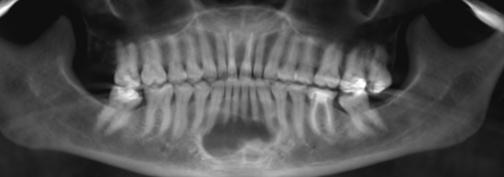

MarchApril 2026 ISSUU by Florida Dental Association - Issuu